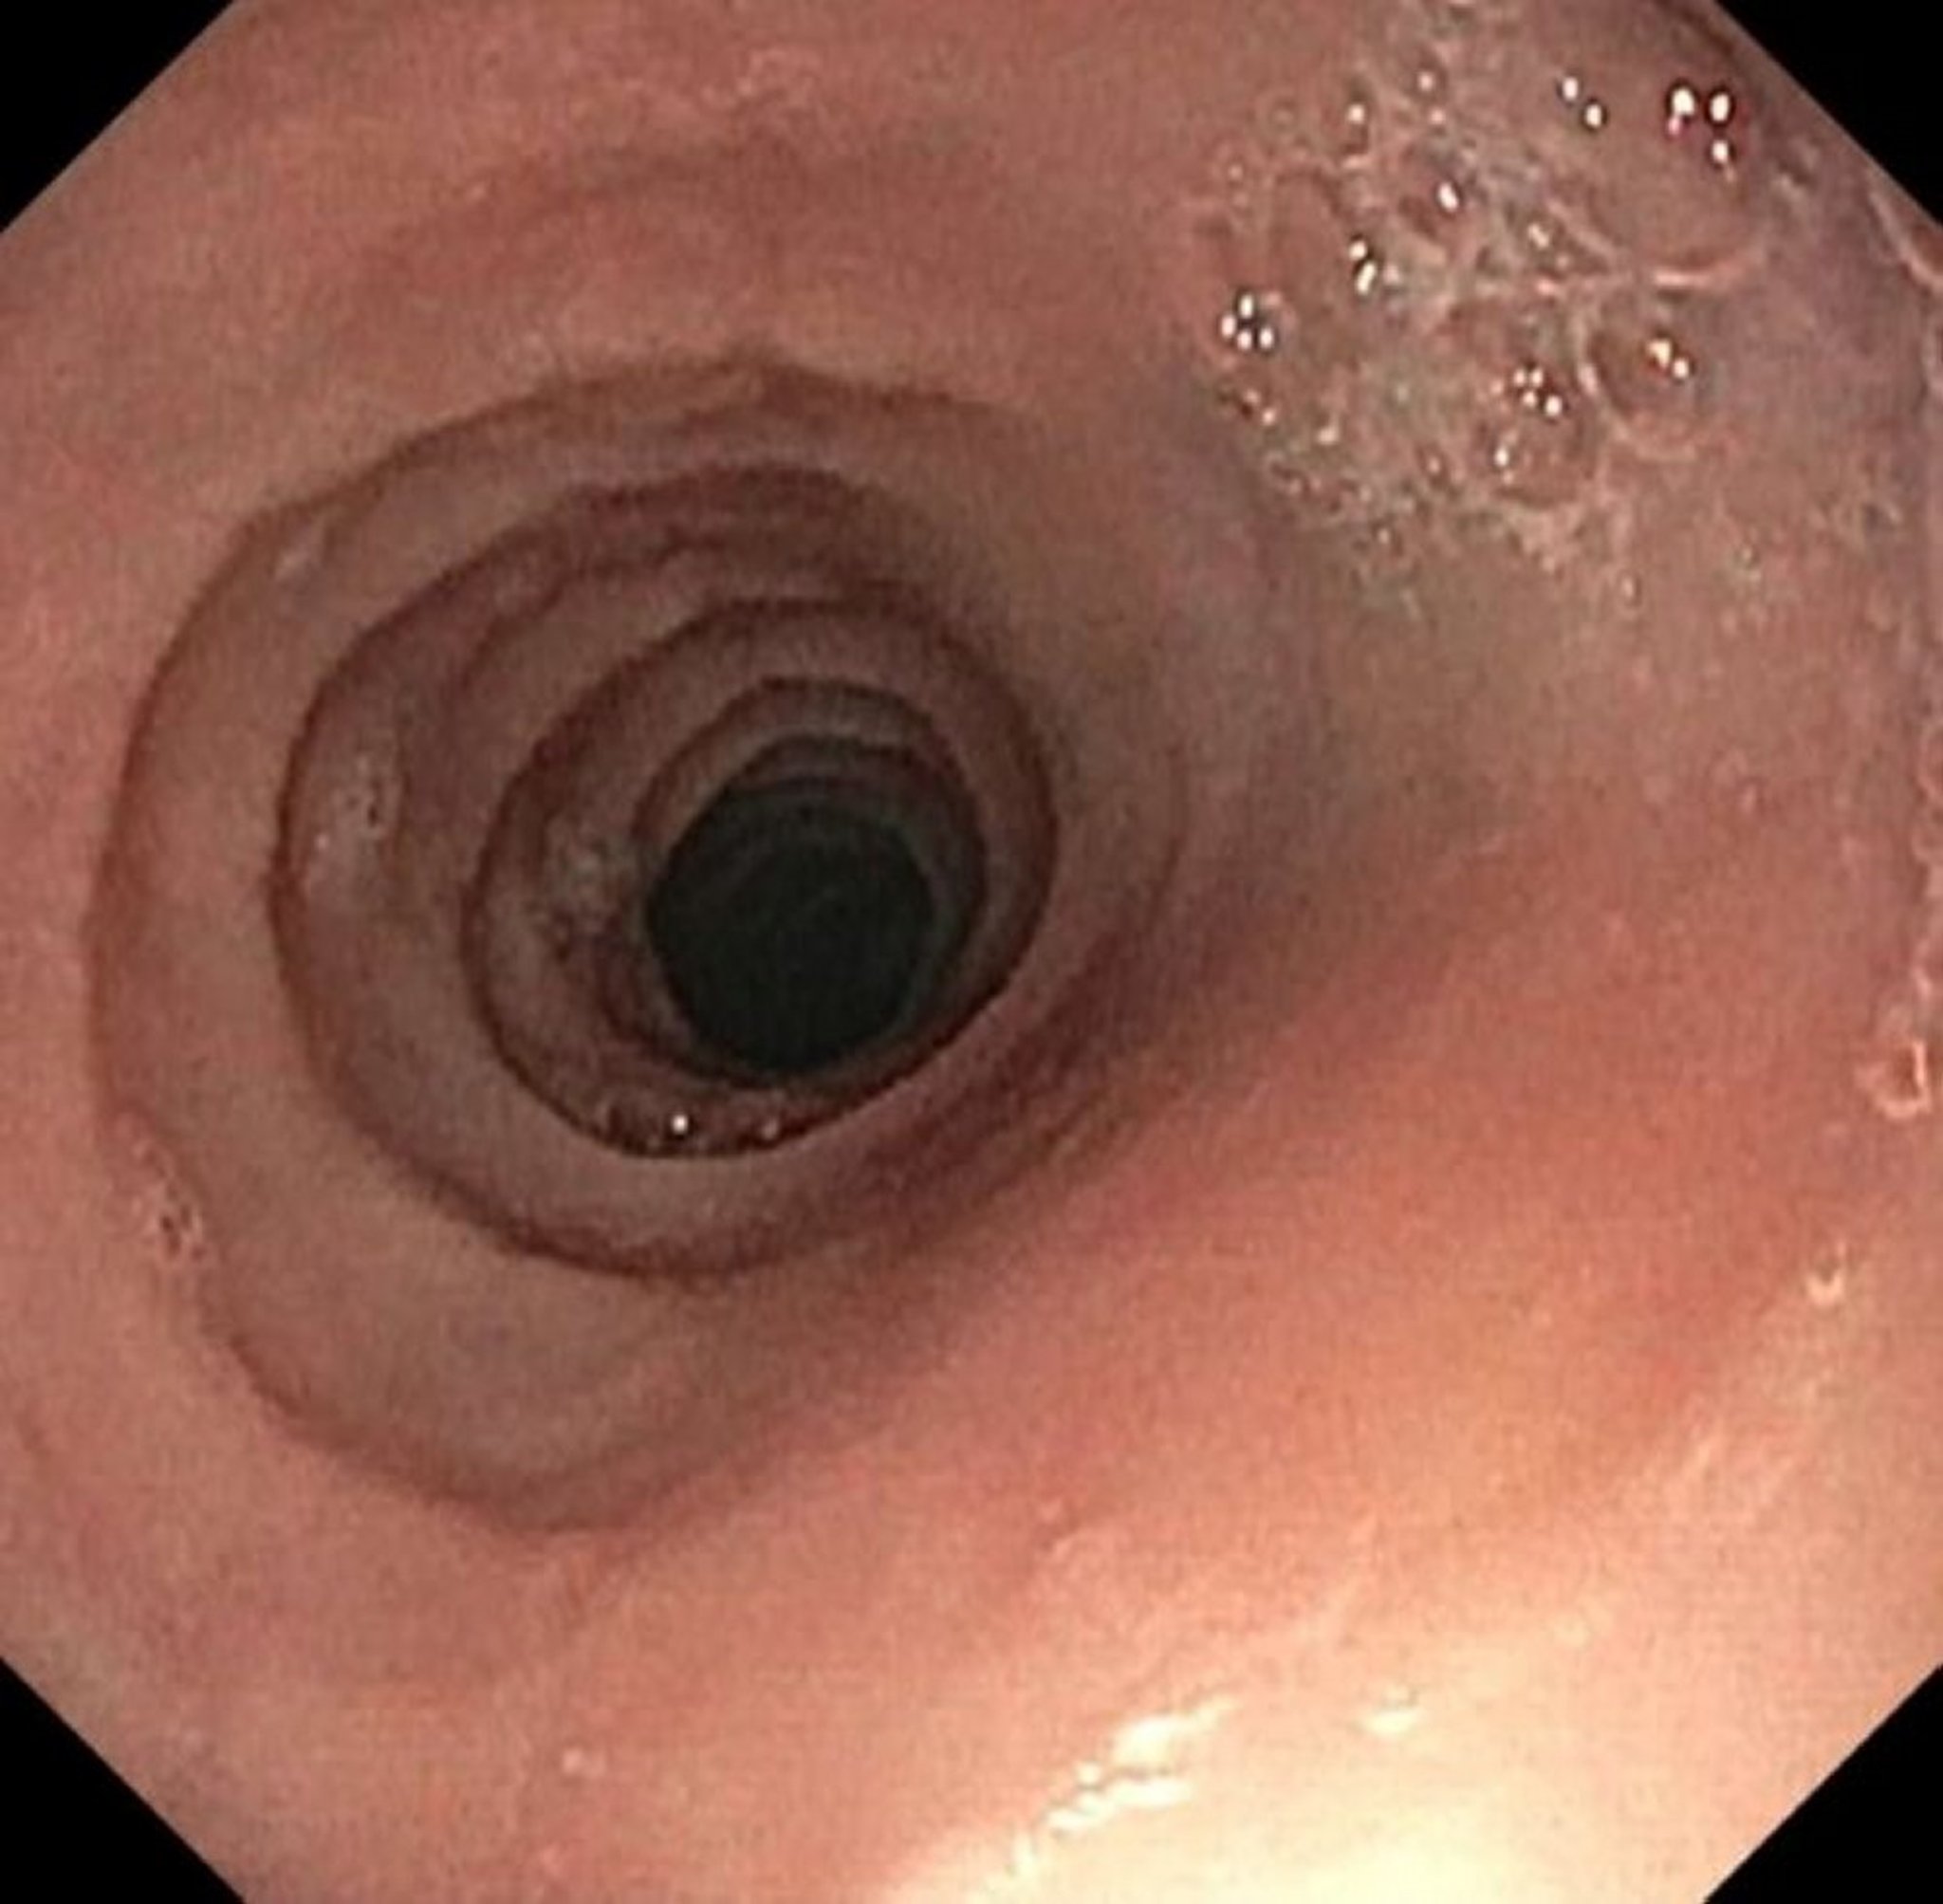

Rings and Strictures in Eosinophilic Esophagitis

Image provided by Kristle Lynch, MD.

Eosinophilic Esophagitis